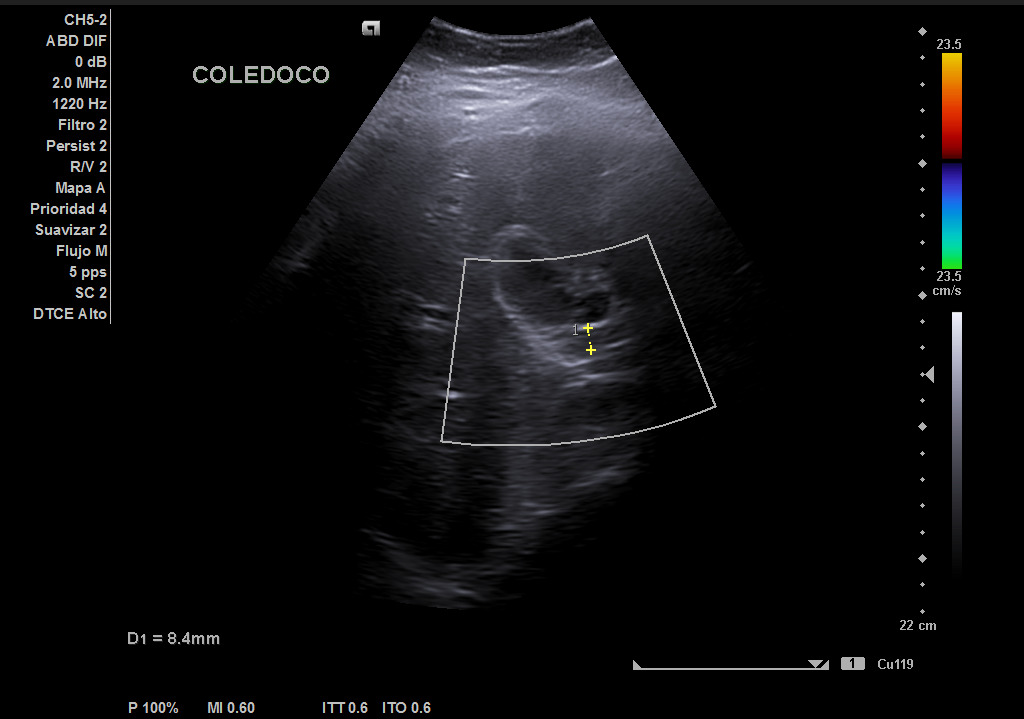

Hígado de tamaño, forma y ecoestructura conservadas, con parénquima homogéneo. Vena porta de calibre conservado. Colédoco dilatado, de 8,8 mm. Vesícula biliar de paredes gruesas y edematizadas (5,4 mm) en cara posterior, con contenido ecogénico y 2 microlitiasis en su infundíbulo.